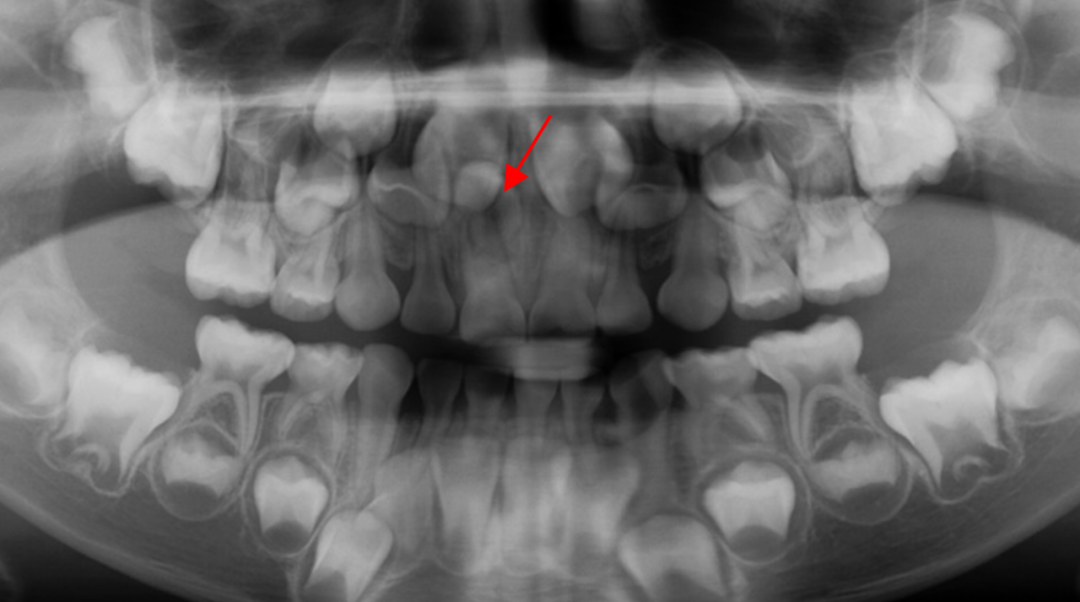

巴西米纳斯吉拉斯州一名11岁女孩被发现口中竟有多达81颗牙齿,引发医学界震动。该罕见病例由巴西联邦大学Juiz de Fora的医生团队记录,并于近日发表在《美国正畸与颌面外科杂志》上。

女孩原本只是前往牙科打算拔除残留的乳牙,X光检查却发现她不仅有18颗乳牙和32颗恒牙,还额外长出了31颗“超生牙”,属极罕见的“多重超数牙”病例。

医生通过肉眼观察和全景片/CBCT(三维影像)判断牙齿位置、数量及与神经的关系。